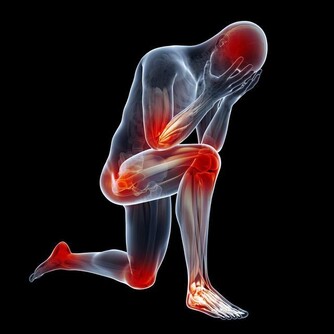

小編說: 明代李時珍在《本草綱目》記載:「艾灸百病、理氣血、逐寒濕、溫經止痛,以三年陳艾為勝」。這裡的「艾」說的就是艾草,大家都認識嗎? 假若說杏是中醫之花,那麼艾便是中醫之草了。艾草有調經止血、安胎止崩、散寒除濕之效。治月經不調、經痛腹痛、流產、子宮出血,根治風濕性關節炎、頭風、月內風等。現代實驗研究證明,艾草具有抗菌及抗病毒作用;平喘、鎮咳及祛痰作用;止血及抗凝血作用;鎮靜及抗過敏作用;護肝利膽作用等,可謂是「萬用之草」。 艾草的功效 艾草性味苦、辛、溫,入脾、肝、腎。全草入藥,有溫經、去濕、散寒、止血、消炎、平喘、止咳、安胎、抗過敏等作用。

看舌苔,明顯發白,月經量少,顏色黯,有血塊。這都說明體內有寒,是最常見的寒性痛經;像這樣的寒性痛經是最常見的,應該是平時常吃涼東西,冷飲、雪糕、冰激凌、冷麵什麼的;或者,常呆在空調開得很足的環境造成的; 痛經的時候,小肚子冰涼是很常見的,不過,有的人喜按,按一下就舒服多了,這是血虛的表現; 而有的人不敢使勁按,使勁按就很痛,這是血淤的表現; 還有人痛經的時候,小肚子不涼反熱,月經量多、白帶多,那是濕熱型的表現。